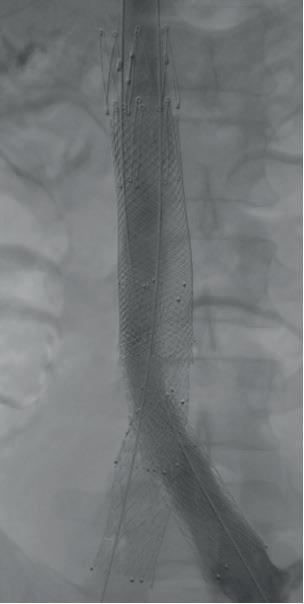

Short of that high bar, significant strides forward have been made. And now, those advances have given way to a randomized controlled trial (RCT) designed to test one of these technologies. Playing on the radiation-free moniker, the RadFree unblinded, multicenter, international study places LumiGuide (Philips), powered by Fiber Optic RealShape (FORS), in a head-to-head with conventional X-ray in a bid to firmly establish that it requires less average fluoroscopy time. Several patients have already been randomized, with the

first receiving treatment using LumiGuide recently carried out by Darren Schneider, MD, at the University of Pennsylvania in Philadelphia. Schanzer is a principal investigator in this 11-site RCT. He has been on the radiation-busting trail for some time. His UMass team was involved in some of the earliest cases of FORS in the U.S., reporting a 75% decrease in fluoroscopy use while carrying out a fenestrated endovascular aneurysm repair (FEVAR) of a thoracoabdominal aortic aneurysm (TAAA). In the period since the technology first received Food and Drug Administration (FDA) approval in 2020, they have been at the center of studies probing its safety and effectiveness, Schanzer details. “We’ve had the opportunity to be involved in several institutional studies looking at our own data and some multicenter studies with other collaborators from the U.S. and around the world, and what we have learned in these early experiences is that use of LumiGuide seems to decrease radiation time, decrease radiation dose, and the hope is that by doing a randomized controlled trial we can definitively show whether or not there is a benefit associated with using this technology.”

used for more and more steps of the procedure. It will be an adjunct to radiation use, but I think that we could potentially cut the dose of radiation more than in half by embracing technologies like this.” The UMass team has completed more than 100 cases

target vessels with LumiGuide’s FORS technology

Such technologies tackle some of the most radiation-intensive steps in complex aortic procedures. “There are certainly many technologies that have come along that have helped decrease the radiation necessary with the more modern, hybrid room setups,” Schanzer continues. “But even as we practice good radiation safety behavior, there still is a significant amount of radiation used for these complex procedures. Where we are with this technology is we can now take a lot of the radiation-intense steps and decrease the use of radiation, and eliminate it for several of these steps.” A case in point: cannulation of the vessels during FEVAR. “This is something that can be done entirely—safely and effectively—using LumiGuide,” he adds.

A series of images shows cannulation of